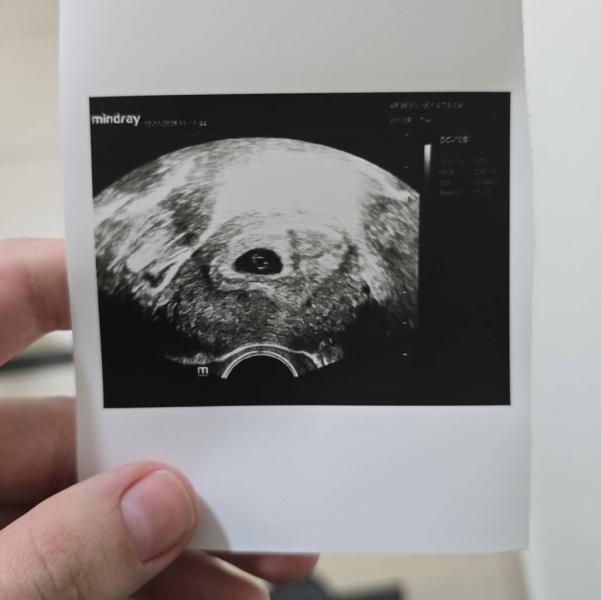

Была сегодня на УЗИ. Нет гематомы, сказали, что те выделения могли быть имплантационными. Спокойно выдохнула. По УЗИ где-то 4 недели 4-6 дней. Сердцебиение уже появилось. Так интересно было видеть, как оно бьется, и слушать стук.